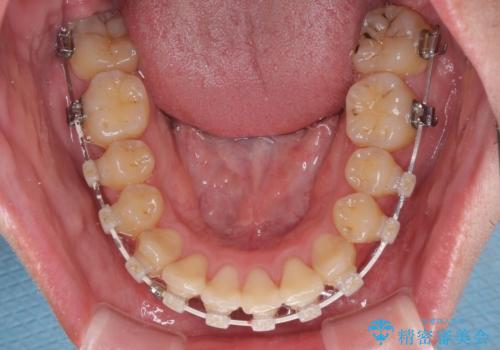

クロスバイトは、治療の過程で咬み合わせが大きく変化する期間があり、食事が取りにくくなってしまいます。

また、装置が対合歯と咬み合ってしまい、頻繁に脱落するなど、色々と面倒なことがあり、治療がスムーズに進まないことがあります。